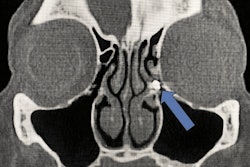

(A) An illustration of the typical location of the distobuccal (DB) root canal orifice in relation to the mesiobuccal (MB) and palatal (P) root canal orifices. (B) An illustration of the unusual location of the DB root canal in close approximation of the P root canal. (B, buccal; D, distal; M, mesial.)

Since spatial relationships between the roots and adjacent anatomical structures, as well as their shapes and positions are often difficult to assess using x-rays, a CBCT scan can provide a better understanding of internal root canal anatomy, the authors wrote.